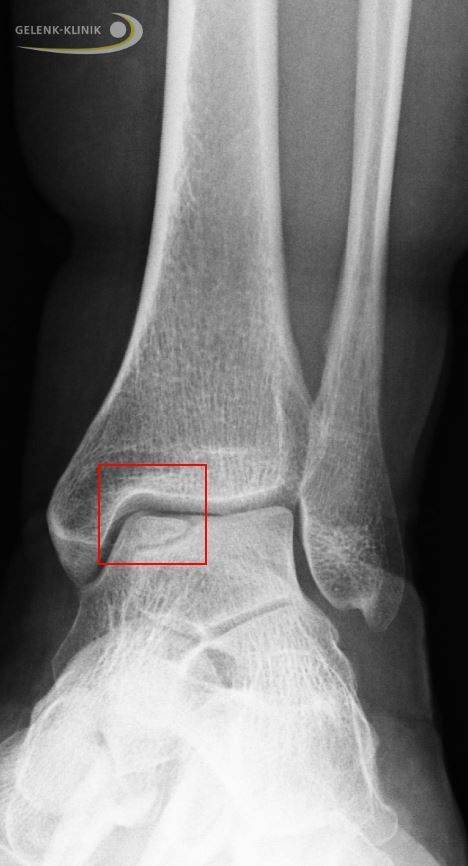

Röntgendiagnostik

Eine Röntgenuntersuchung des stehenden Patienten kann Form, Dichte, Struktur und die Stellung der Knochen darstellen. Hierfür werden folgende Aufnahmen angefertigt:

- Sprunggelenk im Stehen von vorne

- gesamter Fuß im Stehen von der Seite

- Fußes von oben im Stehen

- Saltzman-Aufnahme: eine stehende Aufnahme, die die Stellung des Fersenbeins zeigt

Die standardisierte Aufnahmetechnik hilft Fehlstellungen auszuschließen. Weiterhin kann das Röntgen auch Knochenschäden darstellen. Hierbei ist zu beachten, dass durch die Überlagerung von Knochenstrukturen der Schaden nicht immer gut zu beurteilen ist. Weiterhin kann der Arzt mithilfe des Röntgen Arthrose im Sprunggelenk ausschließen.

Auch eine indirekte Beurteilung des Knorpels im Sprunggelenk ist möglich. Im Stehen kann bei Arthrose der sichtbare Gelenkspalt im Sprunggelenk eingeengt sein: Der Durchmesser des Gelenkspalts im Stehen lässt eine indirekte Aussage über die Festigkeit und die Menge des vorhanden Knorpels zu.